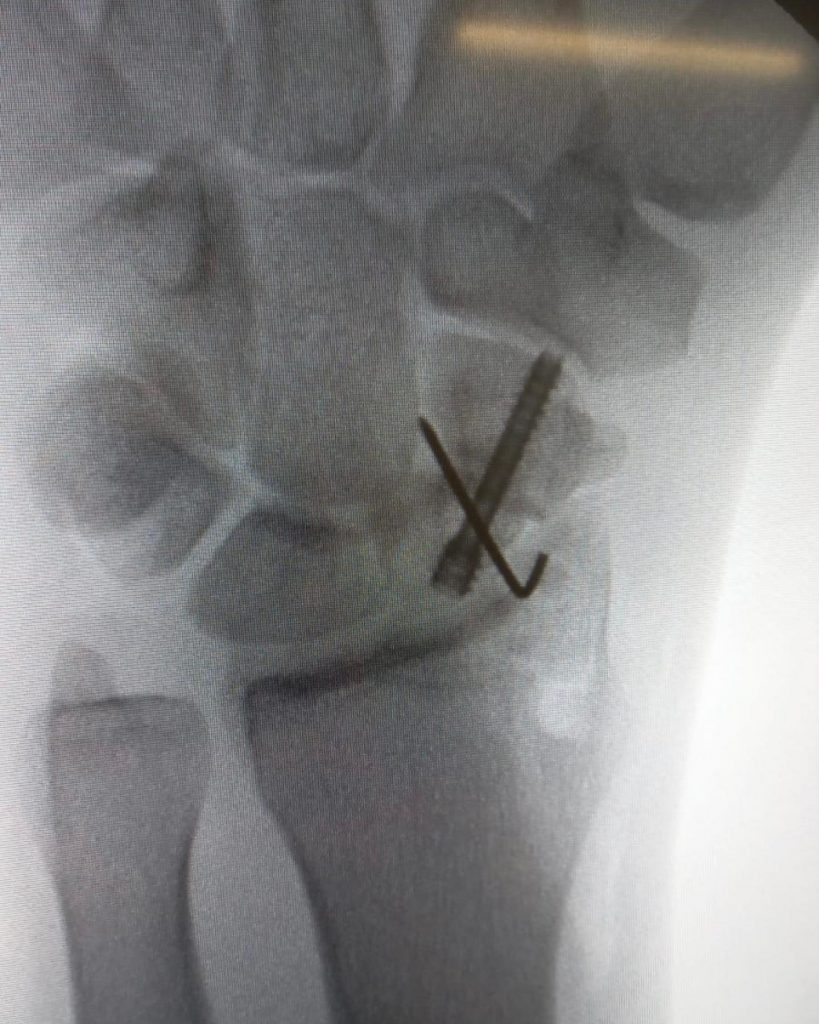

Pseudoartrose do escafóide:A pseudoartrose é uma patologia que ocorre quando não há consolidação de uma fratura após o período esperado – o osso “não colou”.

Nesses casos, é indicado intervenção cirúrgica. É uma situação comum nas fraturas do escafóide.

No caso acima, foi tratada com retalho ósseo vascularizado e fixação com parafuso de Herbert.